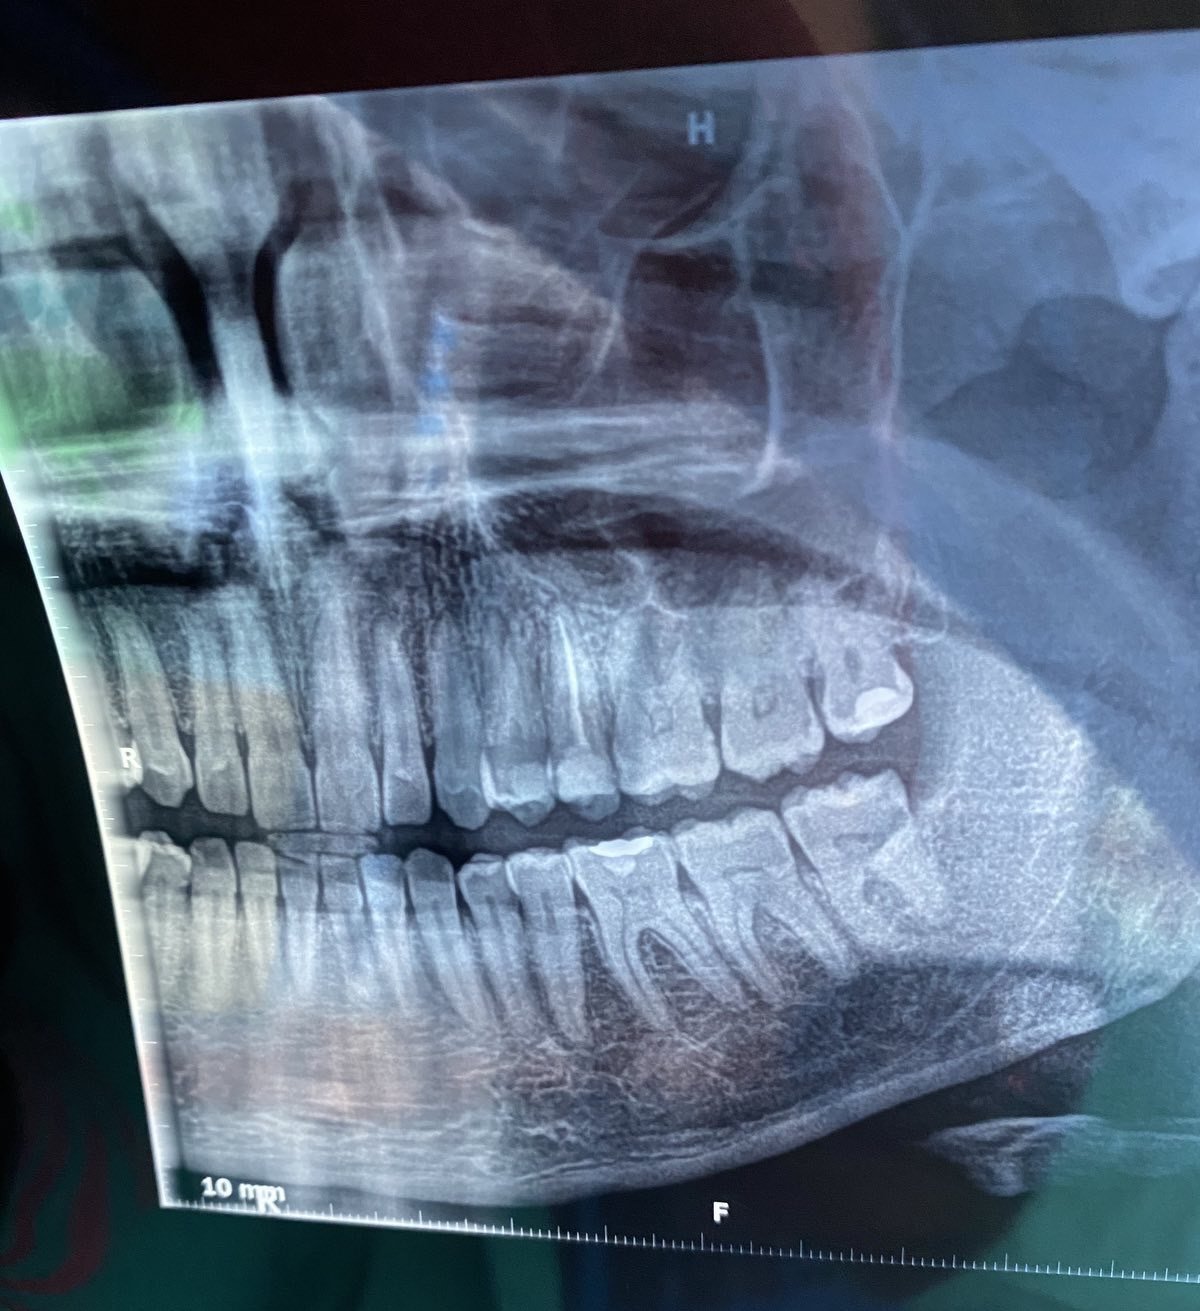

Кое е по-добро - импланти или мостове?

Имплантите и мостовете имат своите предимства и недостатъци. Имплантите често се рекламират, но не винаги са успешни в дългосрочен план. Те изискват определени условия на организма, които могат да увеличат шансовете за успешно интегриране в костта. Освен това поставянето на имплант може да бъде по-скъпо и не гарантира по-голям процент на успеваемост. Мостовете, от друга страна, могат да бъдат поставени по-бързо и по-евтино, но изискват изпиляване на съседните зъби. Всеки случай трябва да бъде оценен индивидуално от имплантолог, който може да предложи най-подходящото решение за конкретния случай.